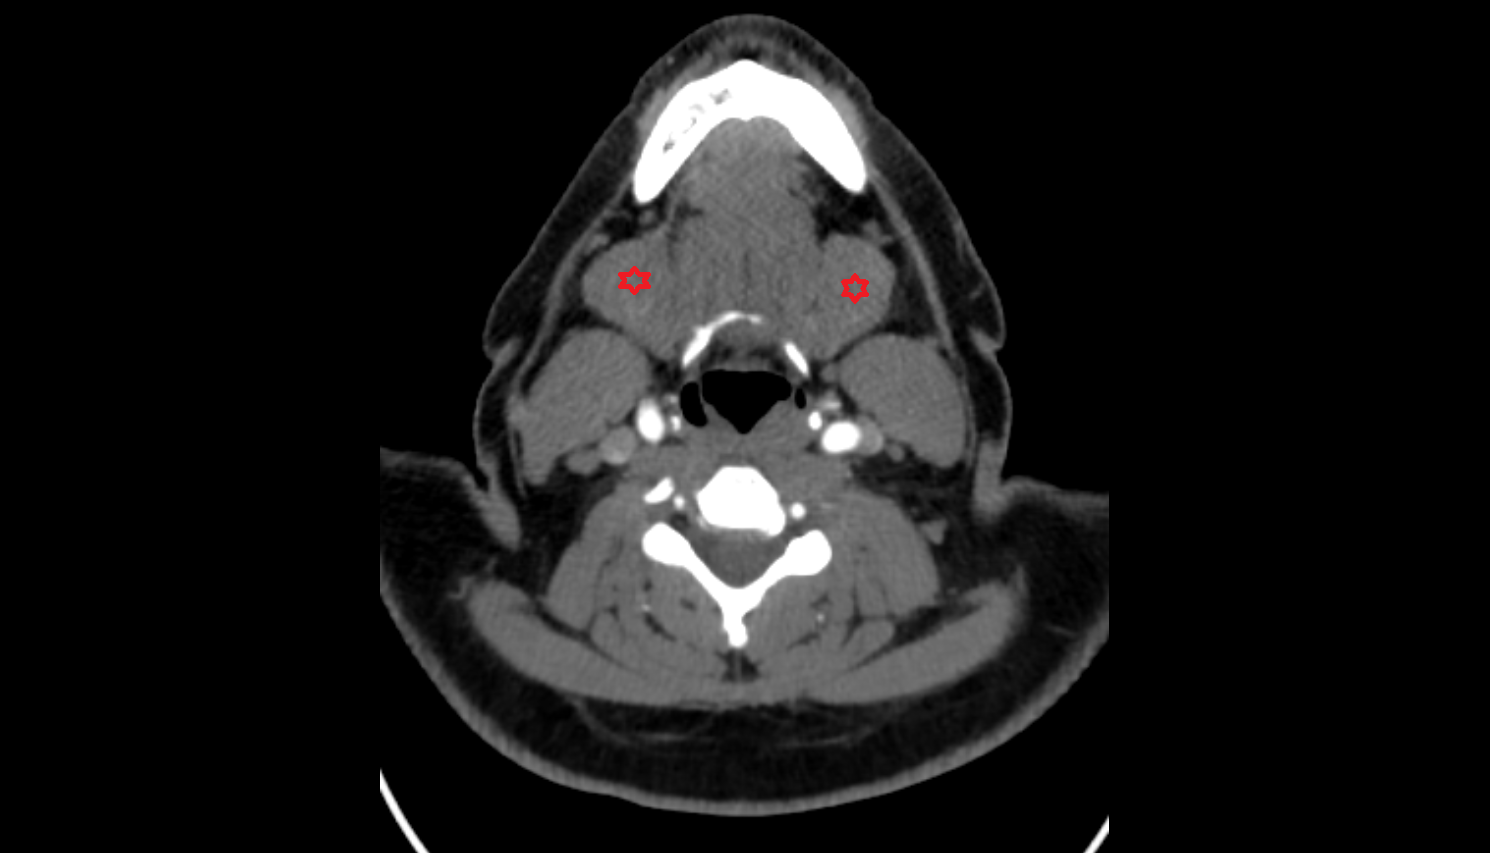

- Submandibular gland